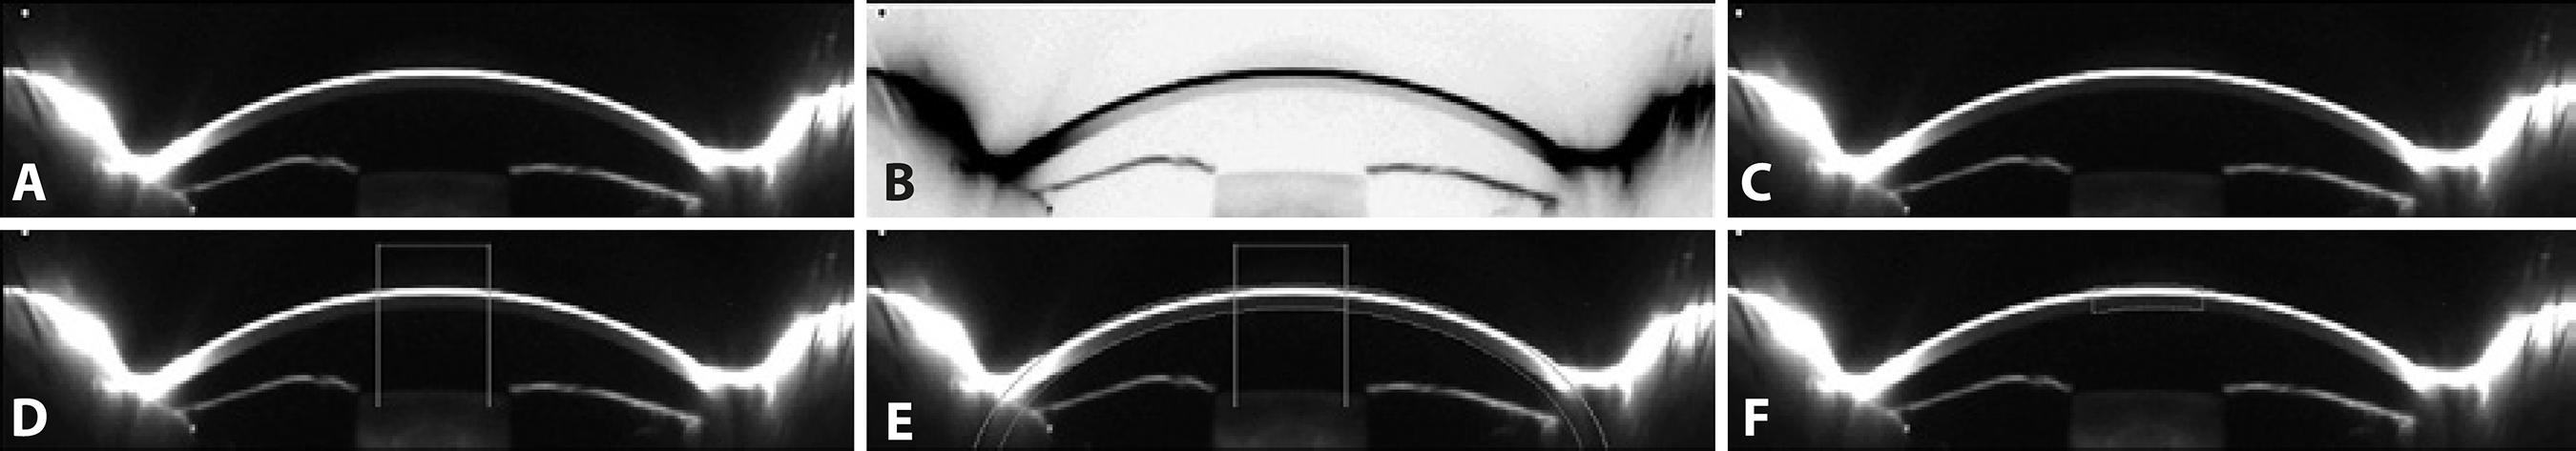

Seven meridians for each eye, with orientations ranging from 70° to 110°, were analyzed. The image for each meridian was first converted into an 8-bit image (Figure 1 A) and then contrast-reversed (Figure 1 B). Finally, the "Invert LUT" tool was applied, which reversed the image contrast and pixel values of the image (Figure 1 C), resulting in pixels with a value of 0 being white and pixels with a value of 255 being black. The grayscale image was calibrated in optical density units (o.d.u.) by the Optical Density Calibration tool of the Image J software. This tool provided a calibrated optical density step table (with a density range of 0.05 to 3.05 o.d.u.) to calibrate grayscale images. We measured the mean gray value to the white background at the left end of each image using the same rectangular selection. We obtained 19 measurements; these were automatically entered into the software's calibrate dialog box and the Image J software then gene rated and displayed the calibration curve. As a result, the image was calibrated to optical density, with white pixels representing the highest optical density (3.05 o.d.u.) and black pixels the lowest (0.05 o.d.u.).

Figure 1 Image processing using Image J. A) An 8-bit image in which pixels with a value of zero are black and those with a value of 255 are white. B) The contrast-reversed 8-bit image. C) The 8-bit image with contrast and pixel values reversed; pixels with a value of zero are now white and those with a value 255 are black. D) Determination of the 3-mm central region. E) Determination of the width of the central region. F) Outline of the 3-mm central region.

The scale was defined by determining the size in pixels of a parameter of known size. A measure of ACD in the center of the image was carried out with the assistance of the "finde edges" tool. As a result, 1mm corresponded to 36,36 pixels.

To determine a 3-mm central region, a central line 3-mm long was drawn and delimited with two vertical lines (Figure 1 D). This region of interest was replicated in each eye. To select the width of the area to be analyzed, and to avoid as far as possible the inclusion of the tear film in the corneal backscatter measurements, we established as a reference point the limit between the corneal endothelium and the aqueous humor, making this reference line coincide with an ellipse that was drawn to delimit the second surface of the cornea, and a band with the CCT value to delimit the first surface of the cornea (Figure 1 E). Finally, the 3-mm central region was outlined (Figure 1 F). The same procedure was performed for the central 5-mm region.